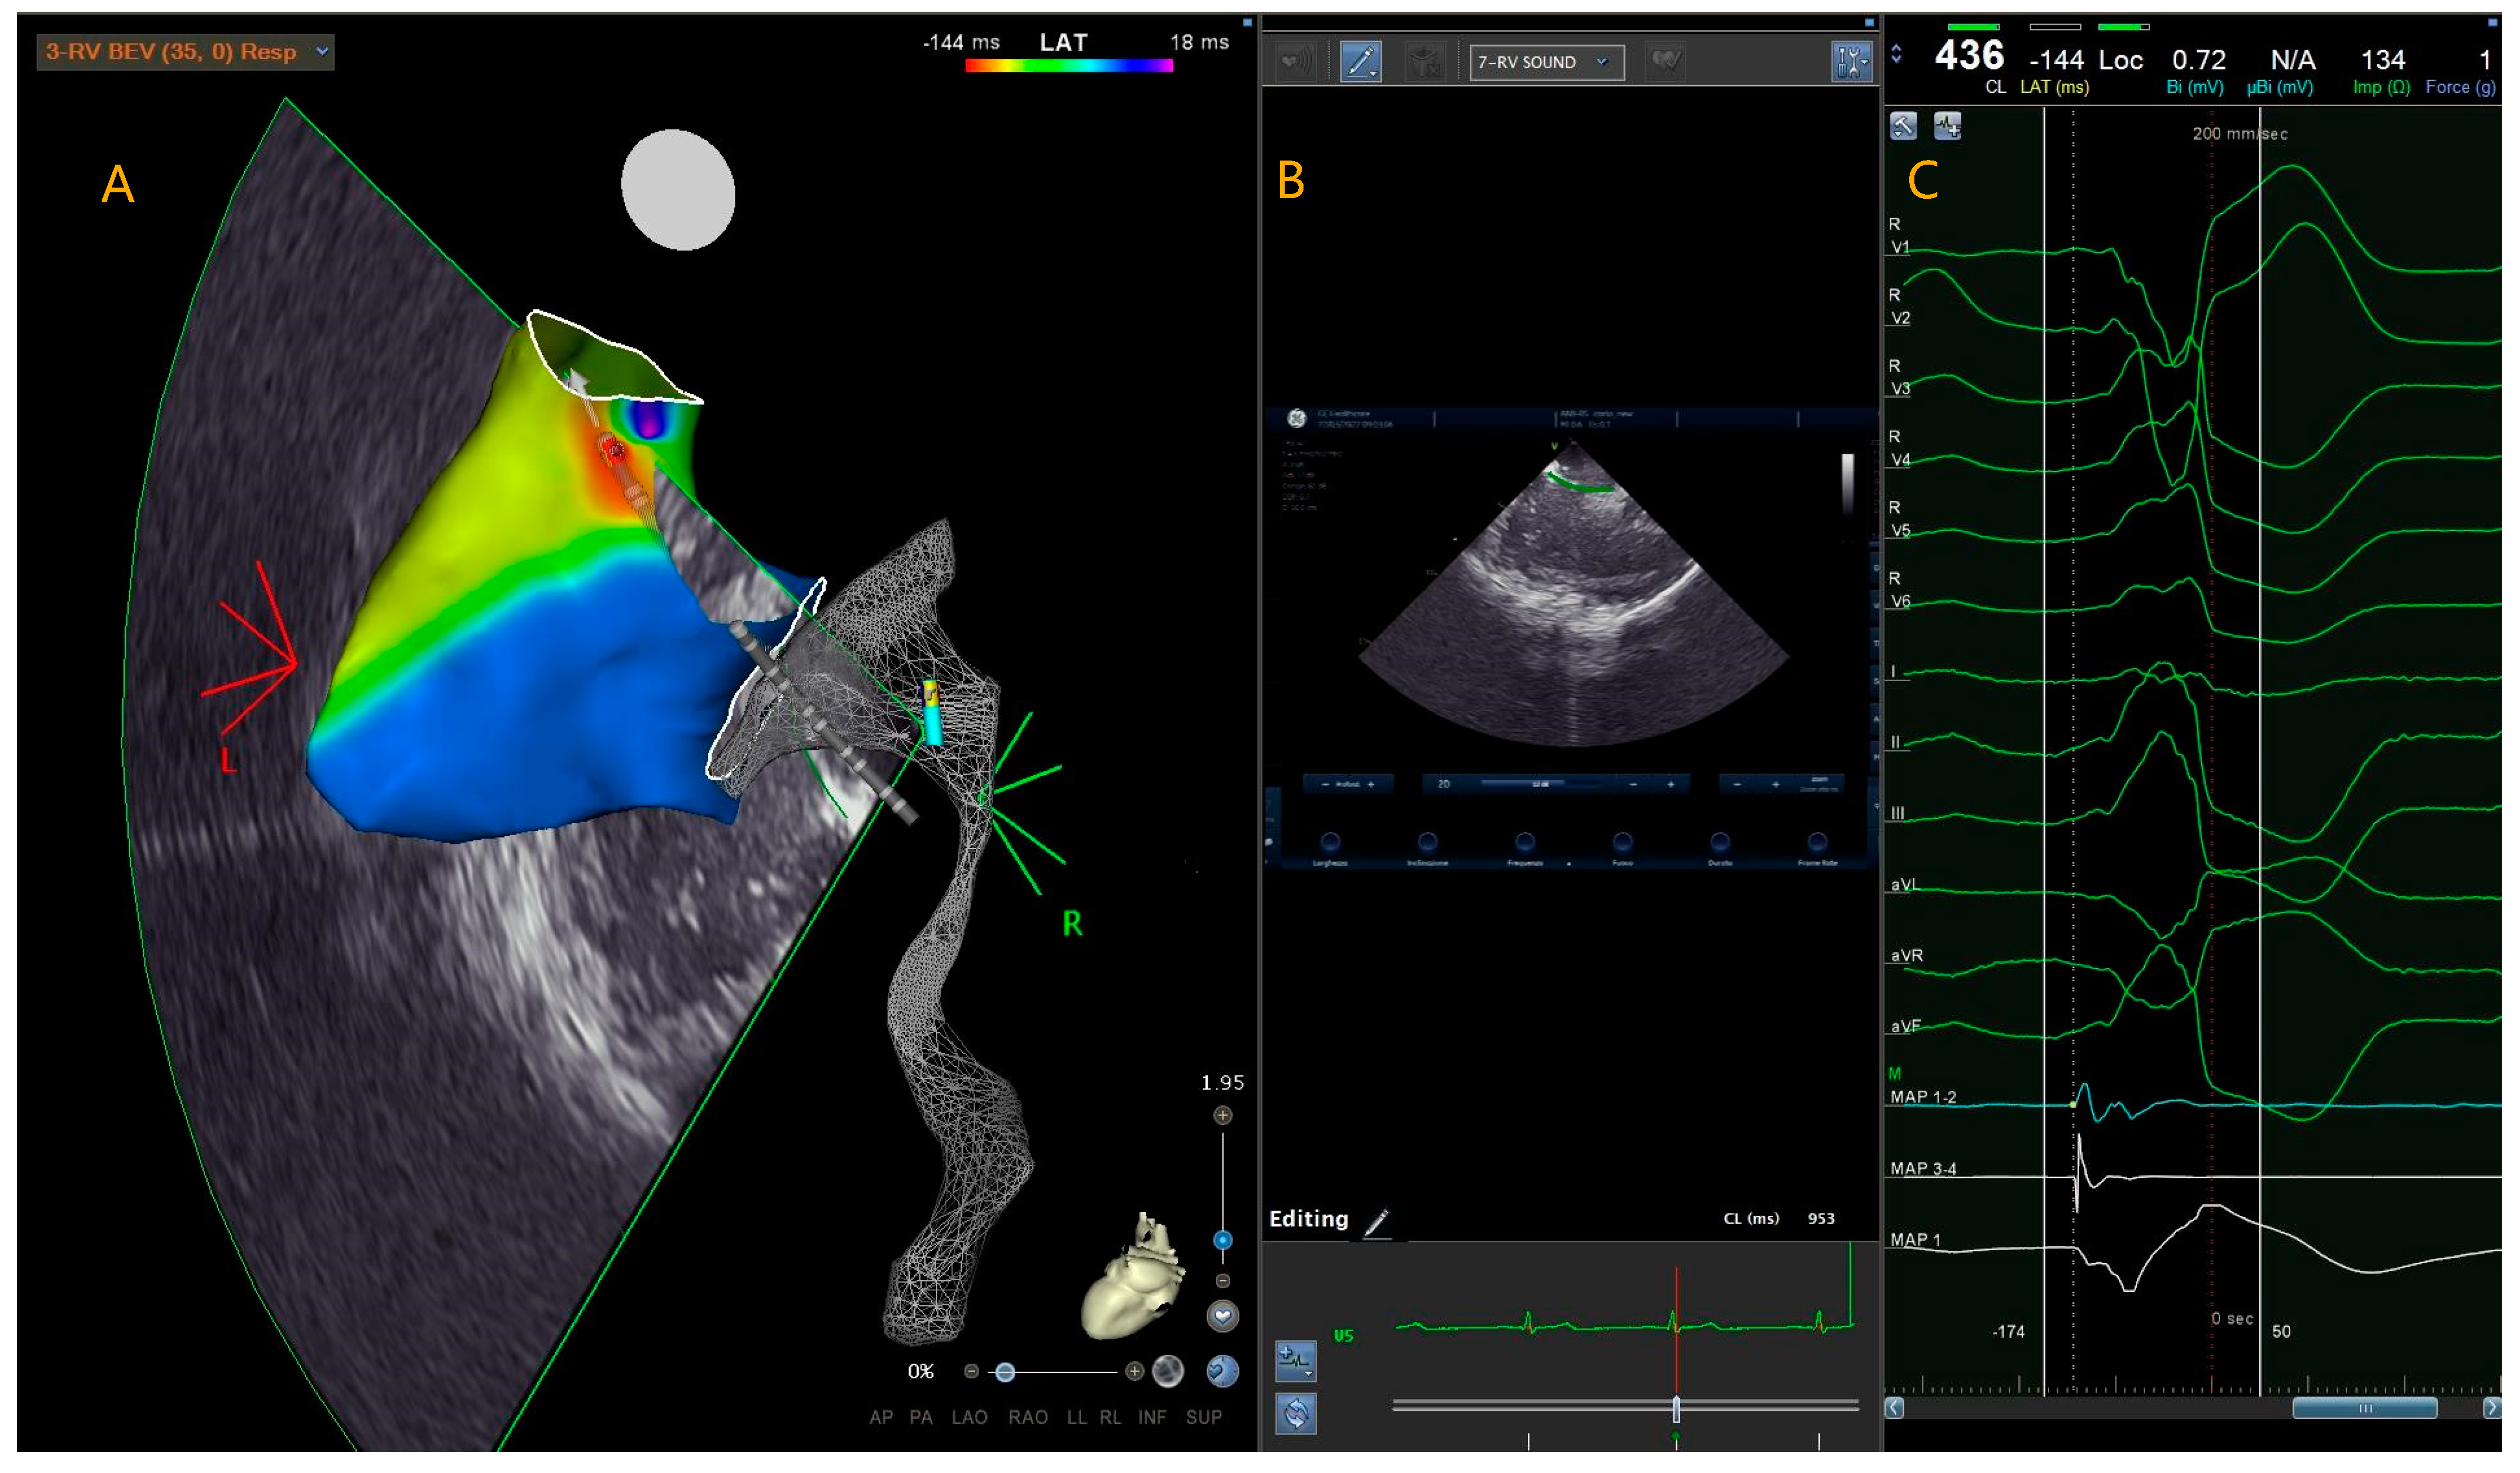

2.3. Radiofrequency Catheter Ablation

3.3. Procedural Data